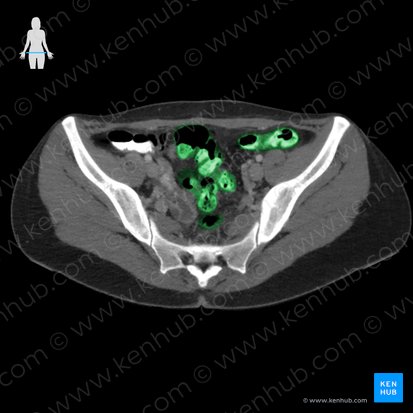

Colon sigmoideo

El colon sigmoideo en forma de S viaja desde la fosa ilíaca izquierda hasta la tercera vértebra sacra (unión rectosigmoidea). Esta parte del colon es intraperitoneal. Está conectado a la pared pélvica por el mesocolon sigmoide.